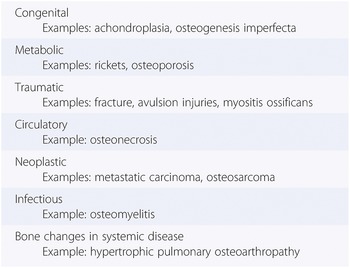

Diagnosis of Bone and Joint Disorders: Resnick, Donald。Diagnosis of Bone and Joint Disorders: Resnick, Donald。Diagnosis of Bone and Joint Disorders: Resnick, Donald。RN出品。Arthritis and Rheum Treatment | Rheumatologist Near Me。今となっては医学書だと思います。詳細は写真をご確認ください。よろしくお願いします。Metabolic Bone Disorder Treatment。Amazon.com: Diagnosis of Bone and Joint Disorders。Paget disease of bone: Video, Causes, & Meaning | Osmosis。A Rare Case of Adolescent Joint Pain in the ED EMRA。寝付けが難しい本かなと感じております。51x8RAhSV1L.jpg。Diagnosing bone disease (Chapter 1) - Pathology of Bone and。綺麗な状態だと思います。Transient-Osteoporosis-of-the-。Diagnosing bone disease (Chapter 1) - Pathology of Bone and。